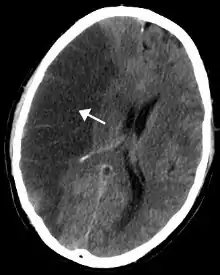

- Cœur et vaisseaux sanguins : la nicotine provoque une accélération du rythme cardiaque et comporte un effet vasoconstricteur, induisant une sous-alimentation des tissus. Athérogène, il entraîne en outre une augmentation du taux de graisse dans le sang. Il favorise directement, à long terme, l'apparition et l'aggravation de l'athérome, obstruant progressivement les vaisseaux sanguins, avec toutes les implications : angine de poitrine, infarctus du myocarde, accident vasculaire cérébral, artériopathie oblitérante des membres inférieurs… Le risque d'infarctus du myocarde est globalement multiplié par 3 chez le fumeur et de manière moindre en cas d'exposition répétée et durable au tabagisme passif. Cette augmentation du risque se retrouve également pour le tabagisme sans fumer (chique, snus)[38]. En cas d'arrêt de consommation de tabac, le risque décroît mais ne revient pas au niveau d'un non-fumeur[39].